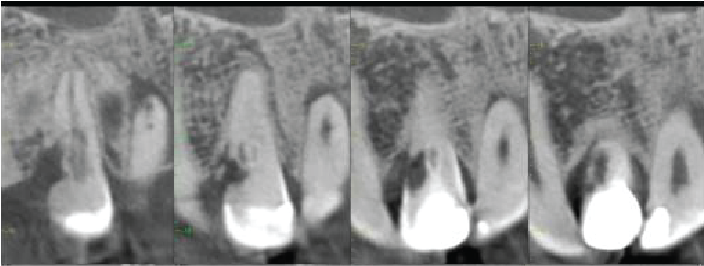

Cross sectional images of UL2

Mesio-distal

Labio-palatal

Oblique (mesio-labial to distopalatal) to show lateral canal

The UL2 has a heavily restored crown. Dens invaginatus anomaly seen (Oehler type I). The root canal is patent. Projections of the root canal pass mesially and distally around the deep part of the invagination and presumably meet on the palatal side. There is also a lateral canal 2.5mm from the apex directed mesiolabially. There is a 7.5mm maximum diameter periapical radiolucency, extending along the mesial side of the root almost to the crestal bone level. The apex is flattened, indicating some apical inflammatory resorption.